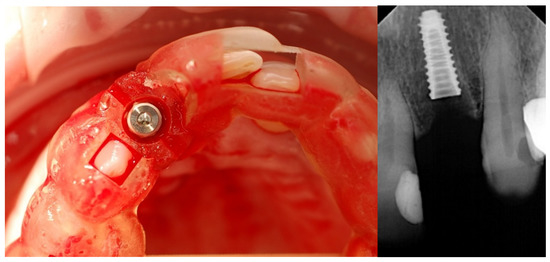

2.2. Surgical Protocol

2.3. Prosthetic Protocol

2.4. Outcome Measures